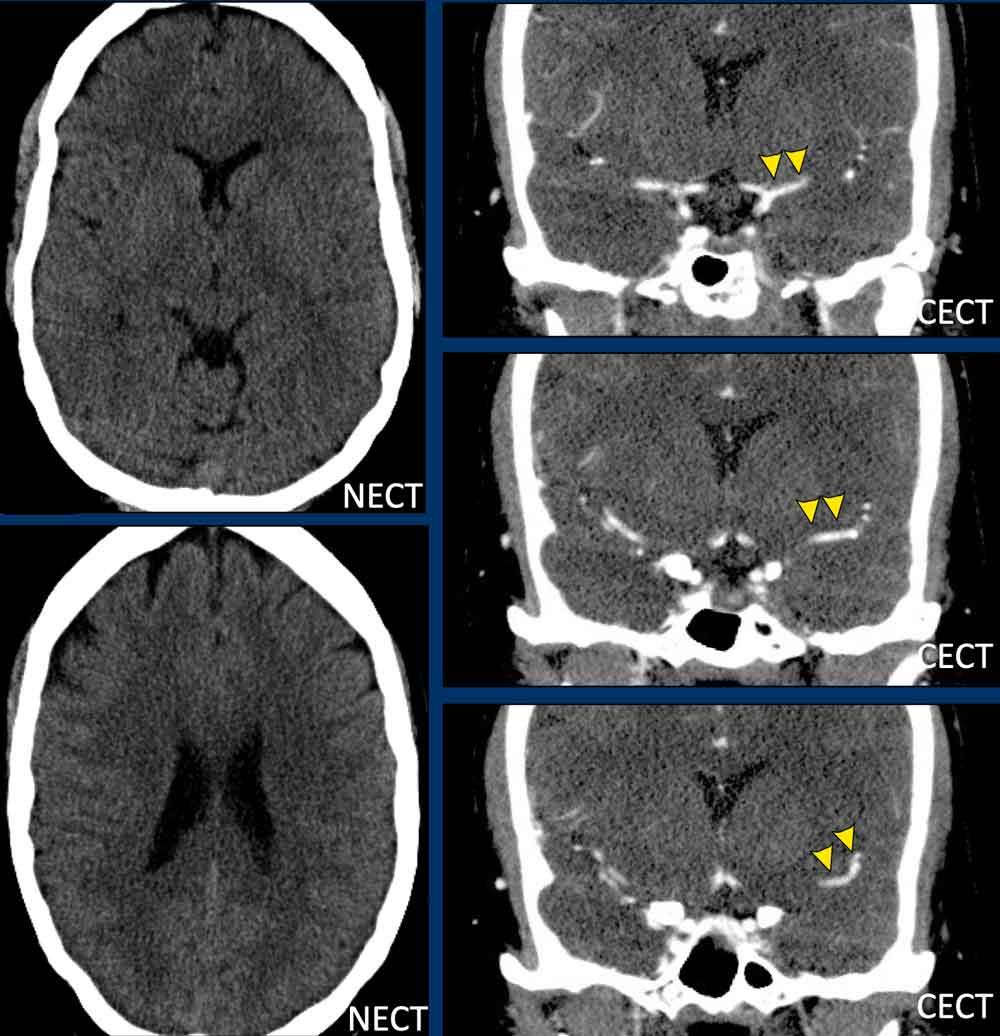

Ca lâm sàng

Một phụ nữ 35 tuổi nhập cấp cứu với triệu chứng rối loạn ngôn ngữ và liệt nửa tay phải.

Chụp CT sọ não không tiêm thuốc (NECT) không cho thấy dấu hiệu chảy máu hay nhồi máu.

Trên CT có tiêm thuốc cản quang (CECT), các mạch máu nội sọ ngấm thuốc bình thường, nghĩa là không có tắc nghẽn nội sọ.

Trong vòng 20 phút, bệnh nhân được điều trị tiêu sợi huyết đường tĩnh mạch (IV), dẫn đến phục hồi một phần.

Tuy nhiên, một giờ sau, tình trạng xấu đi với liệt nửa người bên phải và mất ngôn ngữ.

Thang điểm NIHSS là 27.

Sau đó, bệnh nhân được chuyển đến trung tâm can thiệp.

Chụp mạch số hóa xóa nền (DSA) ICA trái xác nhận bóc tách (đầu mũi tên) qua hình ảnh cấu hình dạng ngọn lửa ở đoạn gần ICA.

Tiếp theo, DSA của ICA phải và động mạch đốt sống trái được thực hiện.

Chụp mạch ICA phải cho thấy vắng mặt động mạch thông trước (Acom) do thuốc cản quang không đi từ phải sang trái. Ngoài ra, bơm thuốc cản quang vào động mạch đốt sống trái cho thấy vắng mặt động mạch thông sau (Pcom).

Đây là bằng chứng xác nhận chẩn đoán “Động mạch cảnh bị cô lập”.

Giảm tưới máu vùng động mạch não trước và động mạch não giữa (toàn bộ là vùng tranh tối tranh sáng, không có lõi nhồi máu trên hình ảnh CBV – không hiển thị)

Vậy giải thích thế nào về việc động mạch não giữa trái vẫn ngấm thuốc cản quang trong khi ICA trái bị tắc và không có tuần hoàn bàng hệ qua đa giác Willis?

Giải thích là do có các nhánh bàng hệ nhỏ giữa động mạch cảnh ngoài (ECA) và ICA.

Lượng máu này đủ để làm đầy động mạch não giữa bằng thuốc cản quang, nhưng không đủ để tưới máu thích hợp cho bán cầu não trái.

Điều này được thể hiện rõ ràng trên hình ảnh tưới máu.

Trong quá trình can thiệp, lưu lượng máu được phục hồi do vạt nội mạc được tái định vị bởi thao tác của ống thông.

Đặt stent động mạch cảnh được cân nhắc nhưng không thực hiện.

Bệnh nhân được điều trị bằng Fraxiparine.

Sau 24 giờ, thang điểm NIHSS là 2 với chỉ còn mất ngôn ngữ nhẹ; sau 3 tháng, NIHSS giảm xuống 0.

MRI theo dõi sau một tháng cho thấy nhồi máu nhỏ thùy trán trái (mũi tên trắng).

ICA trái thông và còn lại hình ảnh tụ máu trong thành mạch với tăng tín hiệu trên chuỗi xung T1W (đầu mũi tên).